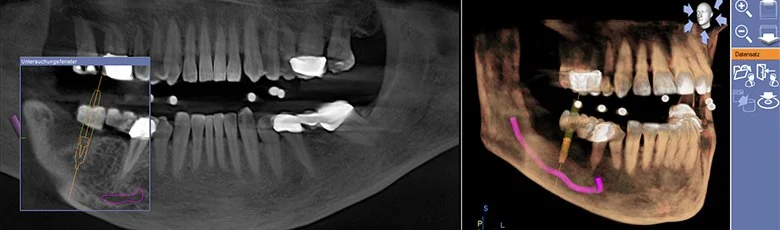

sirona galileoS Comfort plus CT

Cone Beam CT technology allows us to create a 3D image of your jaw, sinus cavity, skull, and airway in order to achieve the best diagnosis.  One such use is to help plan for precise implant placement.  Integration with the CEREC Omnicam and MC XL Premium milling unit allows for fabrication of a surgical guide in order to facilitate precise placement of the implant body.  Other uses include detecting hard to find canals when performing root canals, diagnosing fractures in teeth, airway analysis for sleep apnea, etc.  This technology is digital, and in dentistry we are looking at hard tissues, so compared to a traditional CT in a hospital setting the amount of radiation necessary to produce a 3D image is approximately 100x less!  Another perspective; pilots who fly every day of the year are exposed to the equivalent of 72 Galileos scans per year.

3D Jaw Analysis for Implant Planning